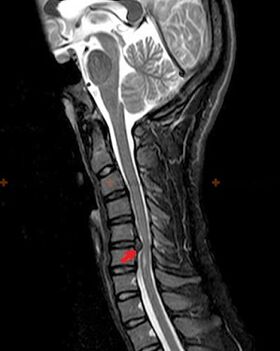

Diagnosis and X-ray signs

Osteochondrosis is an X-ray diagnosis because detailed clinical images are only available when it worsens, and changes in the spine can occur despite a person's complete subjective health.Without X-rays, we can only talk about suspected osteochondrosis, since similar symptoms can also be caused by other diseases (myositis, vertebral tumors, etc.).

To diagnose osteochondrosis, the following investigation methods can be used: radiography (preferably with functional tests), MSCT and MRI.The latter study is most preferred because it allows one to see very clearly the condition of the intervertebral structures.

The presence of the above changes, as well as changes in the disc structure detected by MSCT and MRI, can serve as reliable markers to confirm the presence of osteochondrosis.